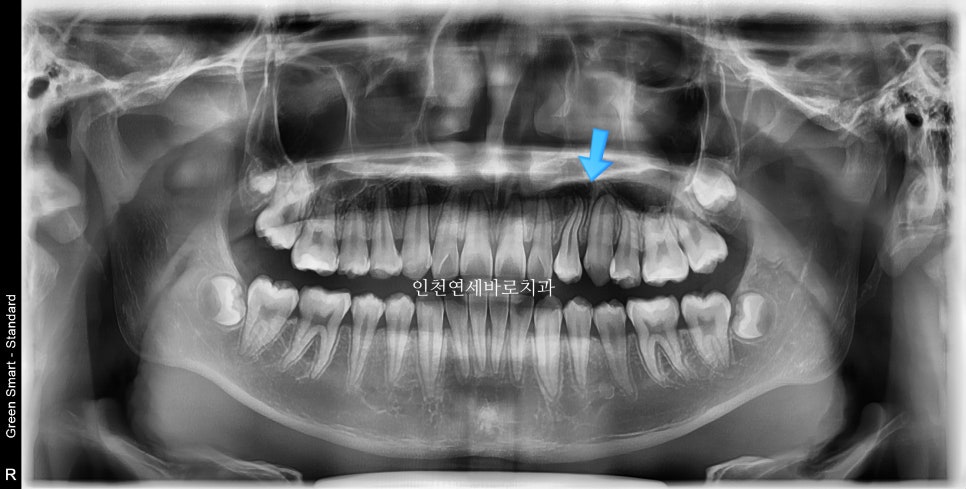

사진상 2 1 3 이라고 표시된 치아의 원래 순서는 1 2 3 입니다.

가끔 이렇게 치아가 만들어지면서 치아의 씨앗 위치가 바뀌면서 뒤죽박죽이 되는 경우가 있습니다.

어느정도라면 원래의 순서로 배열하기도 하지만, 이 친구는 2 1 3 순서로 배열하기로 했어요.

화살표 부분의 치아 순서가 일반적인 순서와는 조금 다르지만

기능적, 심미적으로 거의 문제없이 해결했습니다.